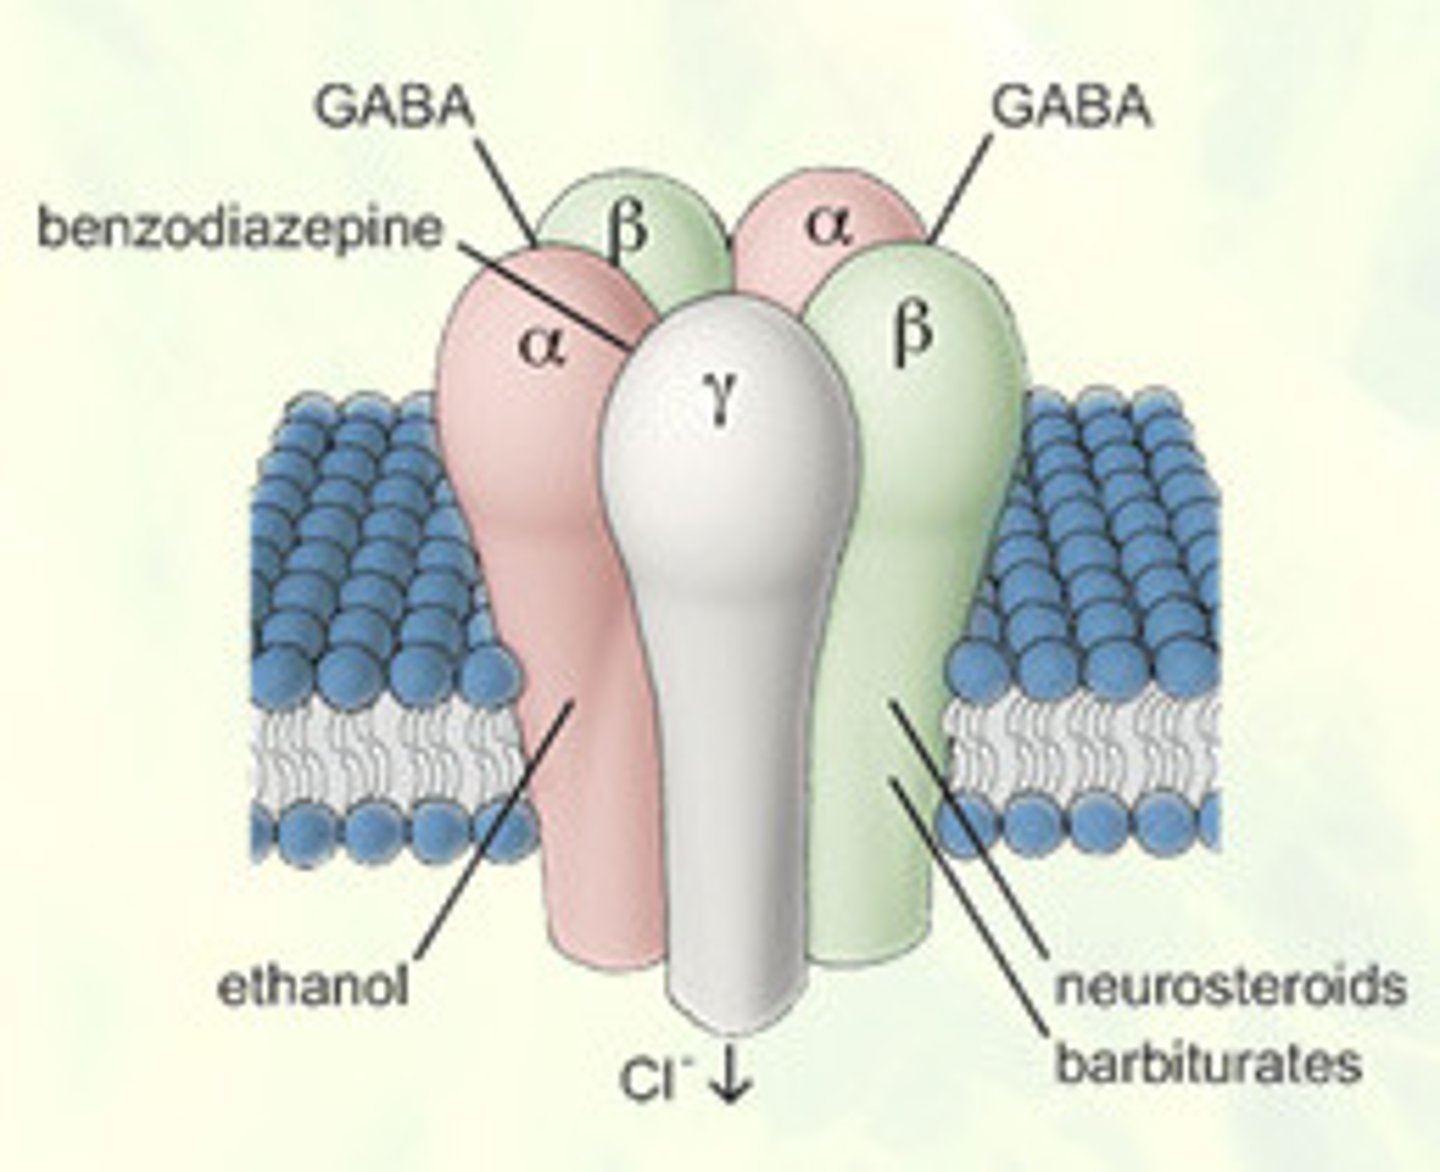

Gamma-aminobutyricvcacidc (GABA)

main inhibitory neurotransmitter in the nervous system

Depressants

drugs (such as alcohol, barbiturates, and opiates) that reduce neural activity and slow body functions

Alcohol

a psychotropic drug (ethanol), usually consumed in a beverage, that slows brain activity, impacting cognition, emotions, and perception